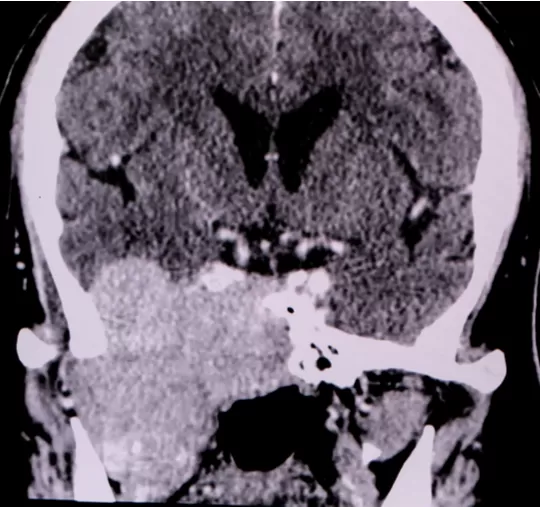

Beyni koruyan ve fonksiyonlarını gerçekleştirmesine katkı sağlayan kafa tabanındaki iyi ve kötü huylu kanser oluşumlarına ileri tıbbi tedavilerle çözüm buluyoruz.

Kafa tabanının ön, orta ya da arka kısmında gelişebilen tümörlerin yerine, yayılım bölgesine, hızına, iyi ve kötü huylu olmasına, hastanın genel sağlık durumuna bağlı olarak yeni nesil tıp teknolojilerinden yararlanarak hassas ve güvenilir operasyonlar gerçekleştiriyoruz. Robotik cerrahiden yararlanarak tedaviden maksimum sonuç alıyoruz.

Kafa tabanı tümörleri; görme bozuklukları, koku bozuklukları, yüz felçleri, yutma güçlükleri şeklinde görülürken beyin sapını etkilediklerinde kolda ya da bacakta kuvvet kayıpları, duyu bozuklukları, yürüme bozuklukları gibi belirtiler verebiliyor.

Beyinde 130 tür civarında tümör çeşidi görülmektedir. Meningiyom beyin tümörlerinin de yüzde 15 ile 20’sini oluşturmaktadır. Kafa tabanında kemik ve kıkırdak dokudan çıkan tümörler de bu gruba girmektedir.